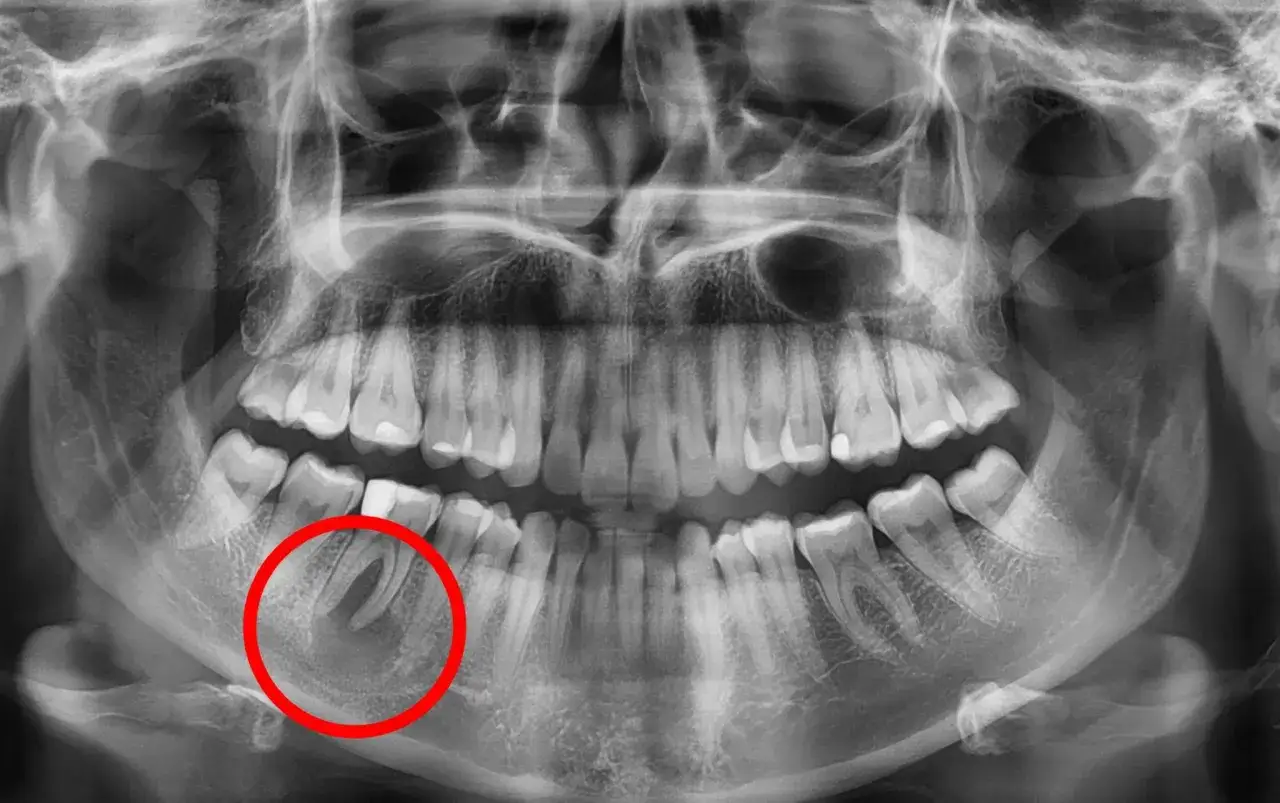

Obrazowanie radiologiczne jest nieodzownym elementem diagnostyki torbieli. Zaczynamy od RTG punktowego, które pozwala szczegółowo ocenić pojedynczy ząb i jego okolicę, uwidaczniając niewielkie zmiany okołowierzchołkowe. Jeśli potrzebna jest szersza perspektywa, wykonujemy pantomogram, czyli zdjęcie panoramiczne, które daje ogólny obraz stanu całego uzębienia, obu szczęk i zatok, co jest przydatne do wykrywania większych zmian. Jednak w przypadku dużych lub trudno położonych torbieli, a także gdy chcemy precyzyjnie określić ich rozmiar, lokalizację i stosunek do sąsiednich struktur, takich jak zatoki szczękowe, kanał żuchwy czy nerwy, niezastąpiona staje się tomografia stożkowa (CBCT). To badanie dostarcza trójwymiarowego obrazu, który pozwala na dokładne zaplanowanie leczenia i minimalizację ryzyka powikłań.